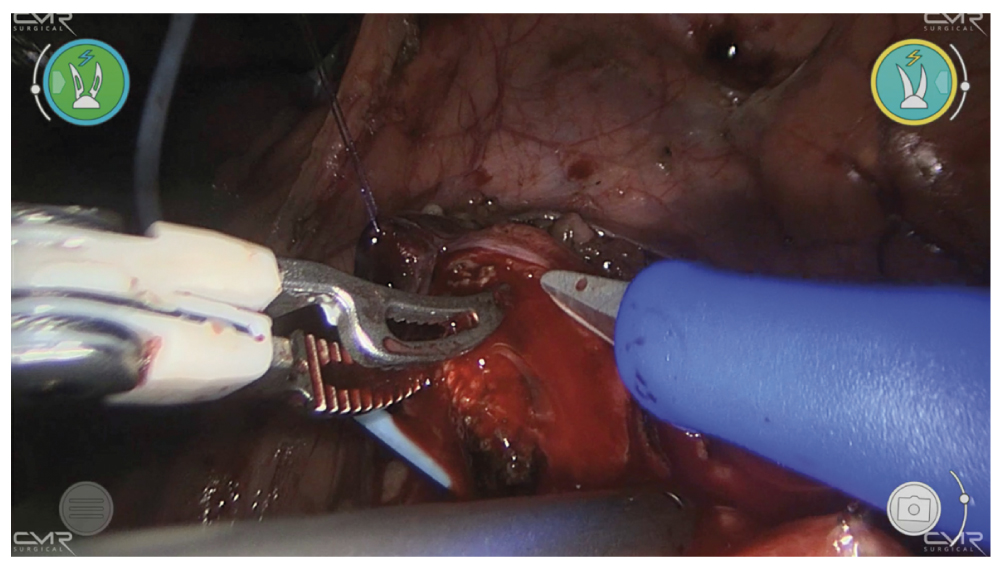

Камень размером 18 × 10 мм визуализирован и извлечён из просвета мочеточника с использованием окончатого атравматичного зажима (рис. 4). Затем он погружён в палец латексной перчатки, доставленной к месту выполнения процедуры, и извлечён наружу. Через катетер, введённый через просвет мочеточника, промывался сам мочеточник и почечная лоханка физиологическим раствором, чтобы удалить фрагменты камней. Конец стента, установленного в мочеточнике, продвинут вверх до уровня почечной лоханки. Продольная уретеротомия закрыта в поперечном направлении путём наложения отдельных абсорбирующихся швов (рис. 5). Рядом с линией швов оставляли дренажный катетер.

Рис. 4. Робот-ассистированная уретеролитотомия. Этап извлечения камня.

Fig. 4. Robot-assisted ureterolithotomy. Stone extraction.